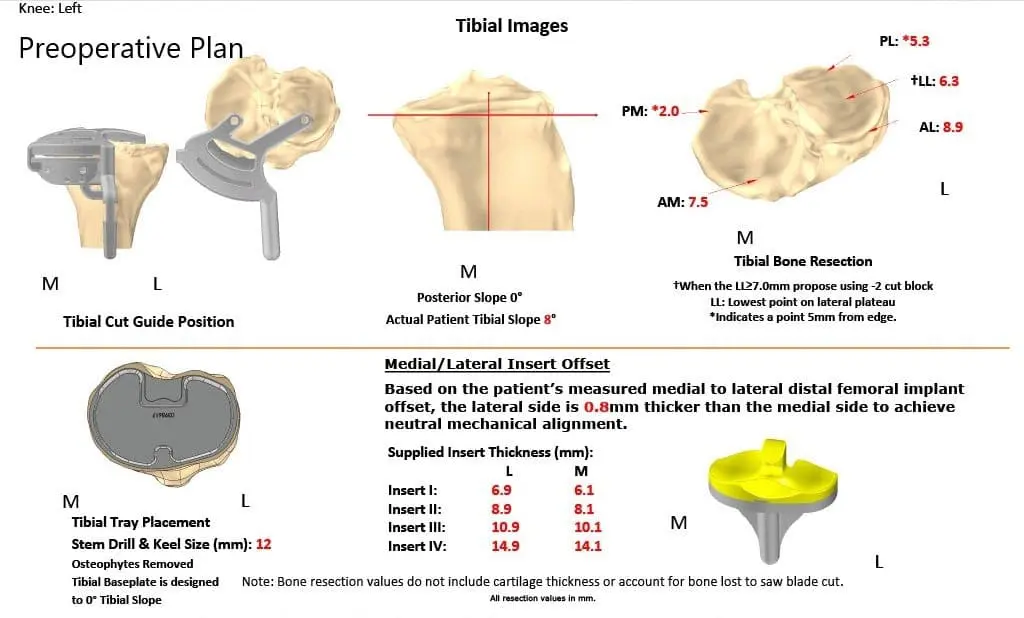

Several weeks before the surgery, a CT scan of the left knee was obtained. A unique 3D reconstruction was obtained from the data. This data was utilized to create unique patient specific implant. Additionally, disposable custom instruments unique for the patient’s knee were constructed. Custom implants and instruments ensured the best outcome of the procedure. A preoperative plan was made specific for the patient’s knee to preplan the bone cuts and offsets.

Complete Orthopedics patient-specific surgical plan for a custom left knee replacement in a 40-year-old male.

Preoperative surgical plan outlining bone cuts and offsets